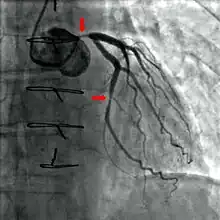

A coronary angiogram (an X-ray with radiocontrast agent in the coronary arteries) that shows the left coronary circulation. The distal left main coronary artery (LMCA) is in the left upper quadrant of the image. Its main branches (also visible) are the left circumflex artery (LCX), which courses top-to-bottom initially and then toward the centre/bottom, and the left anterior descending (LAD) artery, which courses from left-to-right on the image and then down the middle of the image to project underneath the distal LCX. The LAD, as is usual, has two large diagonal branches, which arise at the centre-top of the image and course toward the centre/right of the image.

Coronary angiography of a critical sub-occlusion of the common trunk of the left coronary artery and the circumflex artery. (See arrows)

During coronary catheterization (often referred to as a "cath" or "cardiac cath" by physicians), blood pressures are recorded and fluoroscopy (X-ray motion picture) shadow-grams of the blood inside the coronary arteries are recorded. In order to create the X-ray pictures, a physician guides a small tube-like device called a catheter, typically ~2.0 mm (6-French) in diameter, through the large arteries of the body until the tip is just within the opening of one of the coronary arteries. By design, the catheter is smaller than the lumen of the artery it is placed in; internal (intra-arterial) blood pressures are monitored through the catheter to verify that the catheter does not block blood flow (as indicated by "dampening" of the blood pressure).